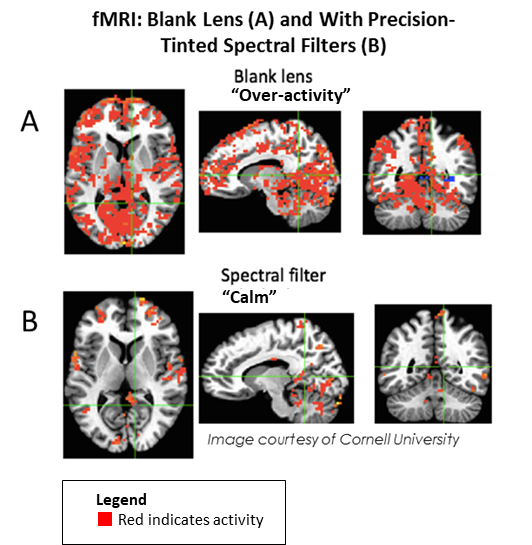

Individuals with Irlen syndrome will often complain of light sensitivity associated with sunlight, bright lighting, fluorescent lights, headlight and glare. They may also have reading problems, as reading becomes inefficient and they may need to re-read for comprehension or build breaks into reading. High contrast (black print on white paper) and visually-intensive activities, create high levels of stress for the brain that trigger physical symptoms which may include headaches and migraines. Brain imaging, both SPECT scans and fMRI, of individuals with this condition shows over-activity, complex brain patterns and non-normalised functioning. This results in a variety of issues, including difficulties reading because of a lack of print stability, issues with glare or discomfort from the white background on the printed page, problems with depth perception and physical symptoms, such as headaches, nausea, dizziness, brain fog, anxiety, strain and fatigue.

Ongoing research by Drs. Adam Anderson and Eve De Rosa at Cornell University’s fMRI facility in the United States shows over-active brain function when Irlen Syndrome sufferers wear a blank lens that normalises when the proper precision-tinted colored filters are worn.